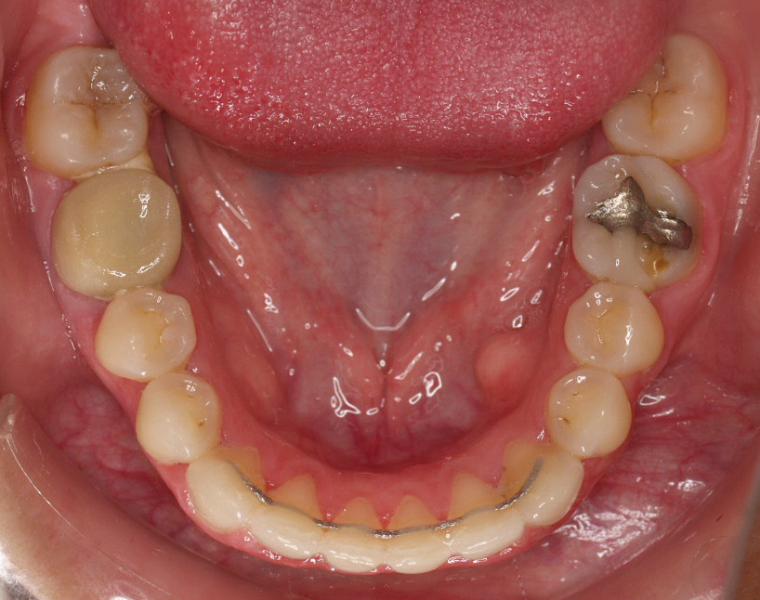

Premolar mandibular incluido + fenestración

45 incluido